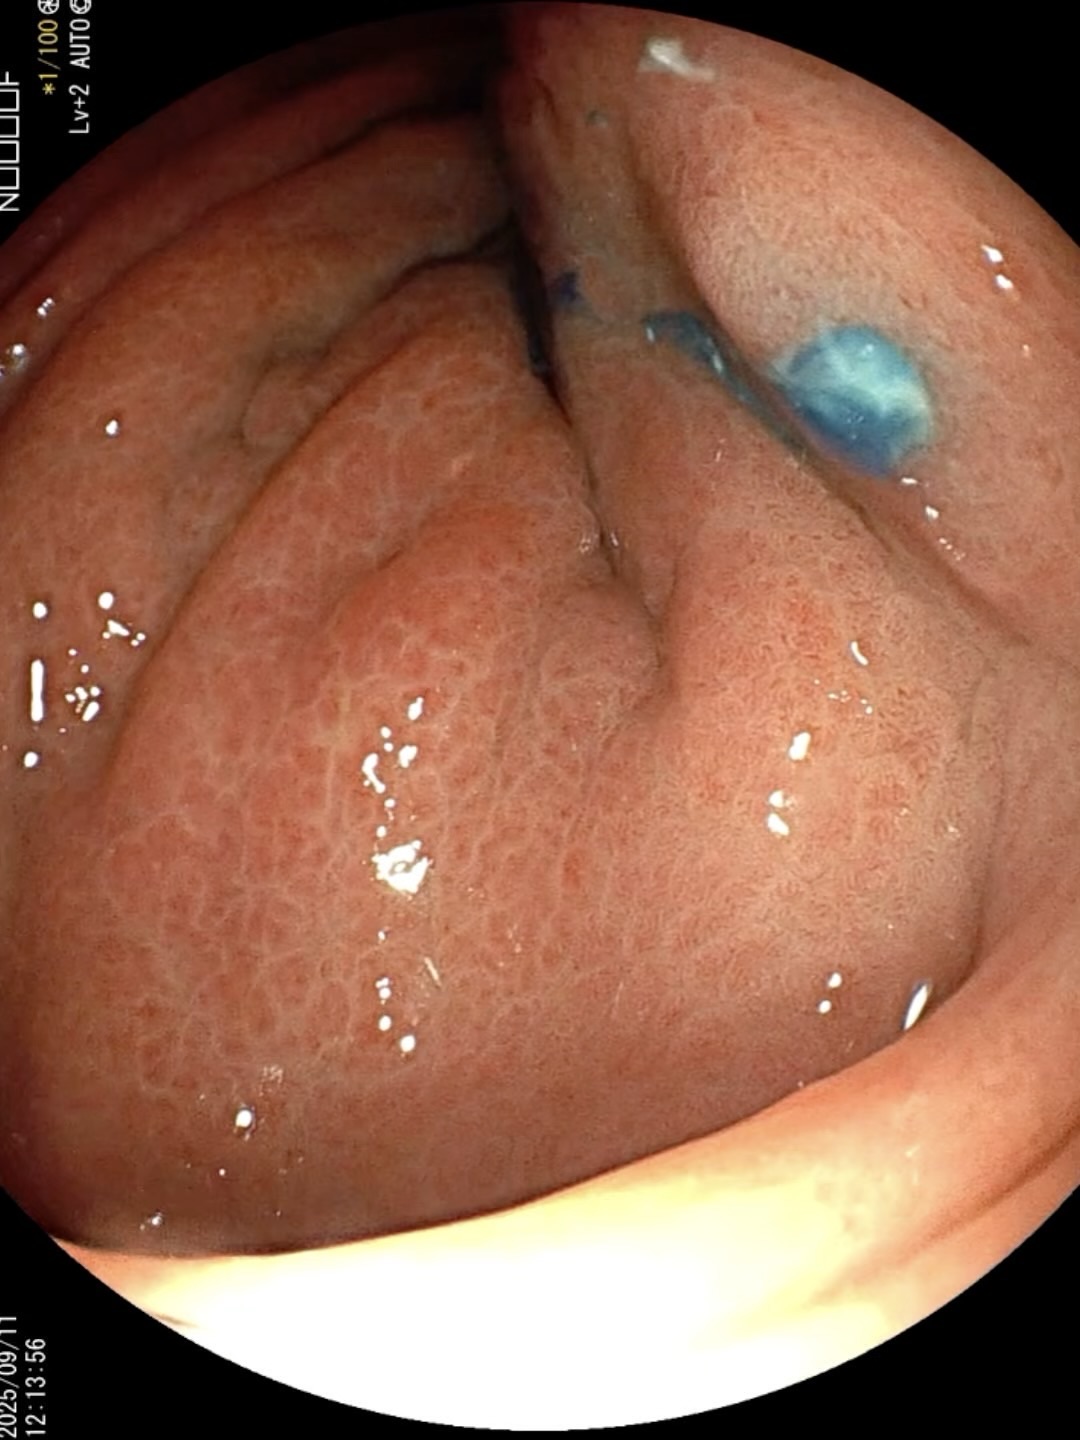

病例胃瘘口-经胃镜下诊断与治疗

患者 老年 男性,腹痛入院。

胃镜诊治如下:

胃瘘 (5)